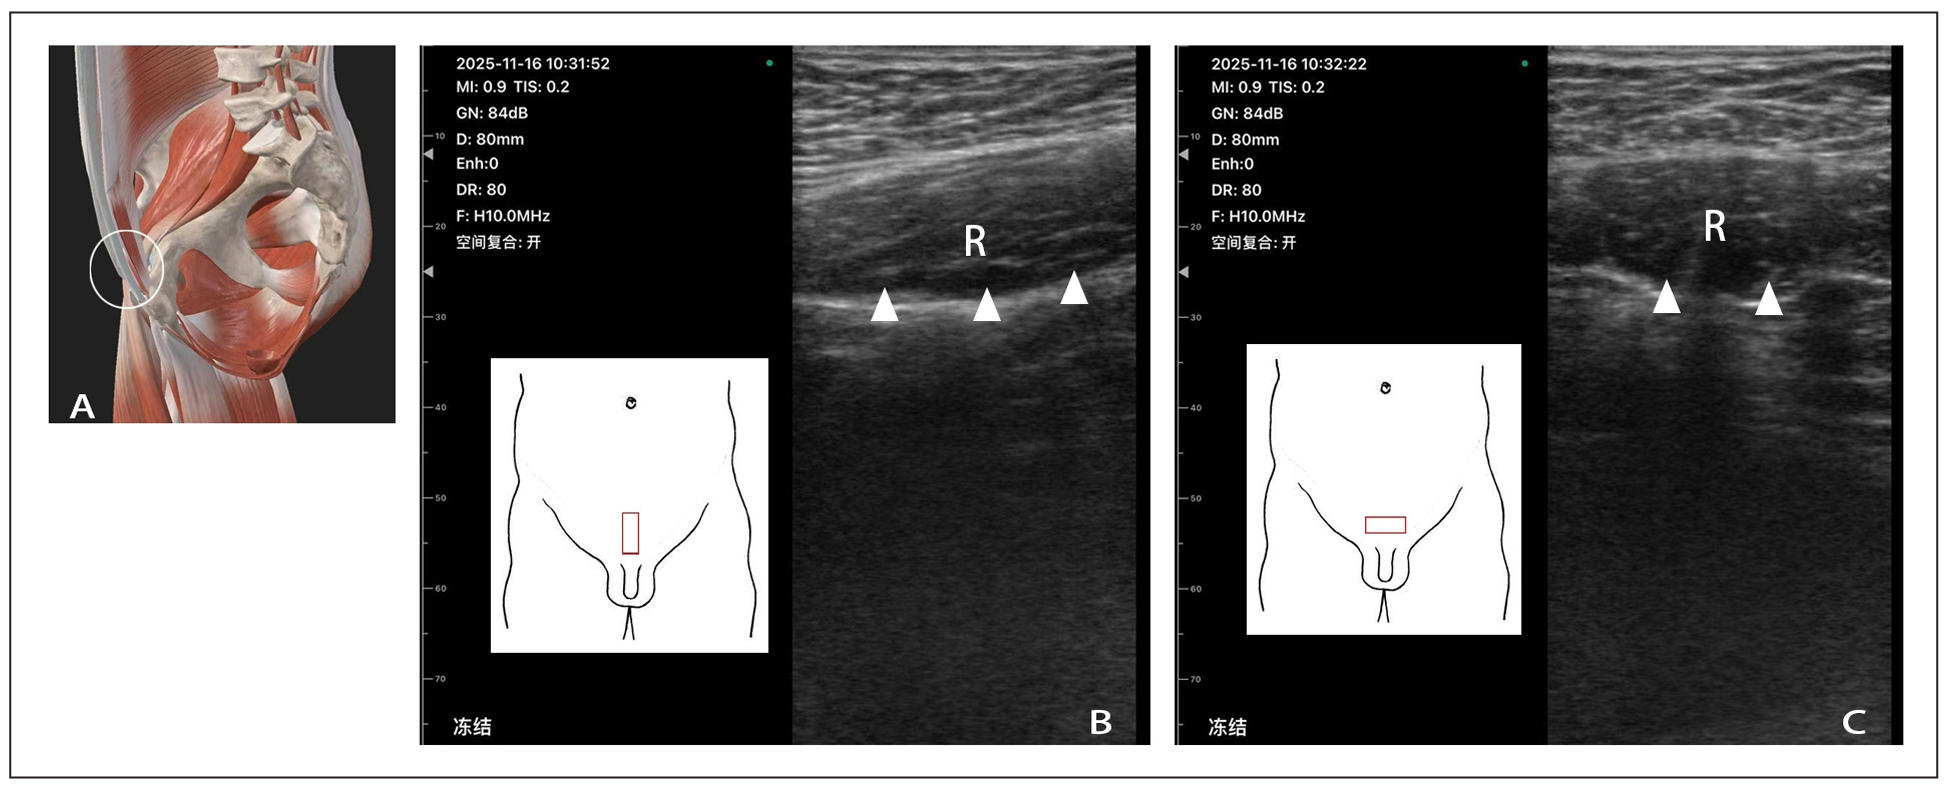

Under the guidance of musculoskeletal ultrasound, we clearly observed inflammatory edema in the muscles of the pubic region in CP/CPPS patients. The Pyramidal muscles and rectus abdominis, situated in the lower abdominal region just superior to the pubic bone, play a crucial role in supporting the pelvic organs and maintaining lower abdominal stability. In patients with CP/CPPS, ultrasound images revealed increased fluid accumulation within these muscles, resulting in a swollen and hypoechoic appearance. The hypoechoic areas indicated the presence of excess fluid, which is a characteristic sign of inflammation (Figure 1).

Figure 1. Musculoskeletal ultrasound scan in the muscles of the pubic region. (A) schematic diagram of anatomical structure; (B) abdominal longitudinal probe scanning; (C) abdominal transverse probe scanning; R: rectus abdominis; the white triangle refers to the area of inflammation and edema. The white circle represents the anatomical structure of the ultrasound scanning area. The red square represents the placement position of the probe

This inflammatory edema in the suprapubic muscles is directly correlated with the lower abdominal pain and discomfort frequently reported by patients. The increased fluid within the muscles exerts pressure on the surrounding nerves and tissues, stimulating the pain receptors. Consequently, patients experience a dull, aching, or sometimes sharp pain in the lower abdomen. We observed that this phenomenon is prevalent in the vast majority of patients who complain of lower abdominal pain. We speculate that prolonged sitting, during which the abdomen folds and compresses at the pubic bone, may be a contributing factor, and this compression can occur regardless of the patient's body weight. It can be alleviated through local muscle relaxation or rectus abdominis muscle stretching exercises. In the past, this pain was often misattributed to factors related to the prostate gland itself, such as prostatic inflammation or congestion. However, our musculoskeletal ultrasound findings have unveiled that suprapubic muscle pathology is an important and frequently overlooked cause of lower abdominal pain in CP/CPPS patients.